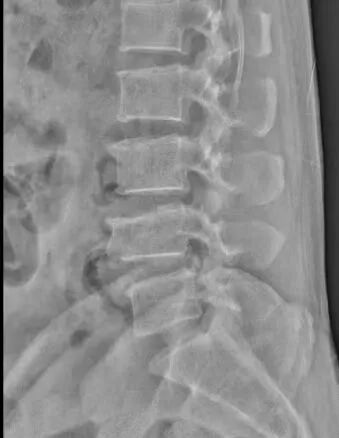

患者江先生,56岁,因外伤4椎体压缩性骨折。为了最大限度减少对患者的创伤,加快其康复,术前科室进行认真讨论,查阅资料,观看手术视频,制订详细的手术计划,于929日在全麻下行微创小切口脊柱后路钉棒系统内固定术治疗腰4椎体压缩性骨折,术后复查X线提示腰椎高度恢复,内固定位置正常。